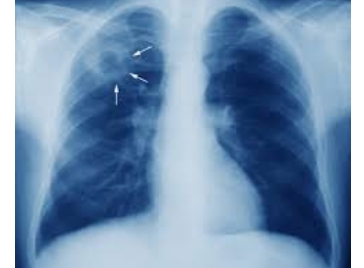

स्वास्थ्य विभाग के मुताबिक कि टीबी उन्मूलन के लक्ष्य को हासिल करने के लिए टीबी उन्मूलन कार्यक्रम के अंतर्गत प्रदेश में चलाई जा रही विभिन्न गतिविधियों का जायजा लेने के लिए केंद्रीय टीम प्रदेश के दौरे पर है। भारत सरकार द्वारा देश में वर्ष 2025 तक टीबी उन्मूलन का लक्ष्य निर्धारित किया गया है, जिसके दृष्टिगत केंद्रीय टीम प्रदेश पहुंची है।

उन्होंने कहा कि टीबी उन्मूलन के लिए केन्द्र सरकार द्वारा निर्धारित लक्ष्य से पहले प्रदेश सरकार ने इसके उन्मूलन का लक्ष्य रखा हैं तथा इस लक्ष्य को हासिल करने के लिए प्रदेश में मुख्यमंत्री क्षय रोग निवारण योजना लागू की गई हैं, जिसके तहत विभिन्न गतिविधियां संचालित की जा रही हैं। उन्होंने कहा कि प्रदेश में टीबी उन्मूलन के लिए किए जा रहे प्रयासों को केंद्रीय टीम द्वारा काफी सराहा गया हैं। प्रदेश में टीबी उन्मूलन के लिए किए जा रहे प्रयासों के परिणामस्वरूप ही राज्य को भारत सरकार ने 24 मार्च, 2021 को देश भर में प्रथम स्थान हासिल करने के लिए पुरस्कृत किया है।